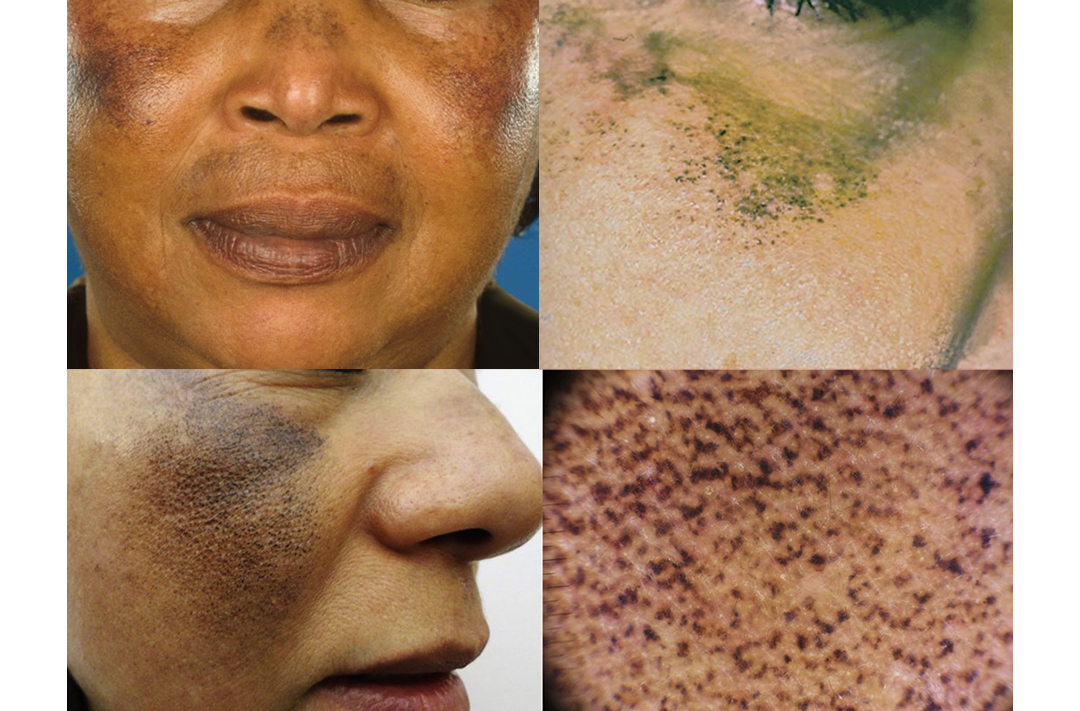

什么是外源性褐黄病(Exogenous Ochronosis)?

外源性褐黄病是由于长期使用对苯二酚成分导致皮肤出现蓝色或深褐色斑点的色素沉着副作用。

由于黑色素过度生成而引发的最典型色素性疾病,表现为形状不规则,

各种大小的褐色斑点主要出现在暴露部位,尤其是脸部。

由于受到紫外线影响,颜色会变深或变浅反复出现,因此建议及早治疗。

黄褐斑类型

主要以左右对称的方式,黑色素沉积在脸颊、额头和眼下等部位,

导致整体肤色暗沉,皮肤看起来不干净。

雀斑类型

大小通常直径在5~6毫米以下,形状为圆形或椭圆形,

也可能呈现棱角分明的形状,并且与周围正常皮肤有较为明显的界限。